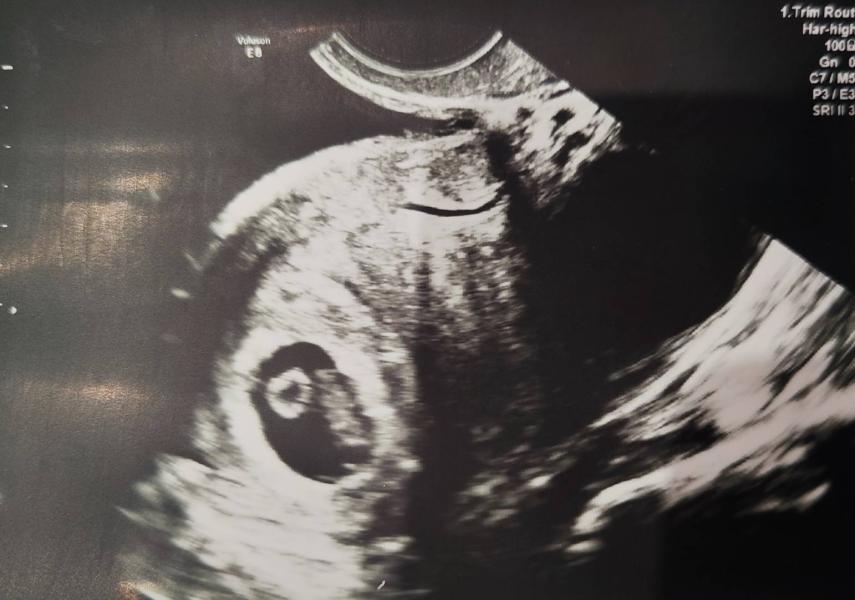

УЗИ на 7,5 недель беременности: первое сердцебиение

УЗИ 7,5 недель - ходила в платную клинику, послушала сердцебиение, распечатали фото, теперь жду когда запишут на первый скрининг в ЖК 🙏 #первыйпост #узи #Киров